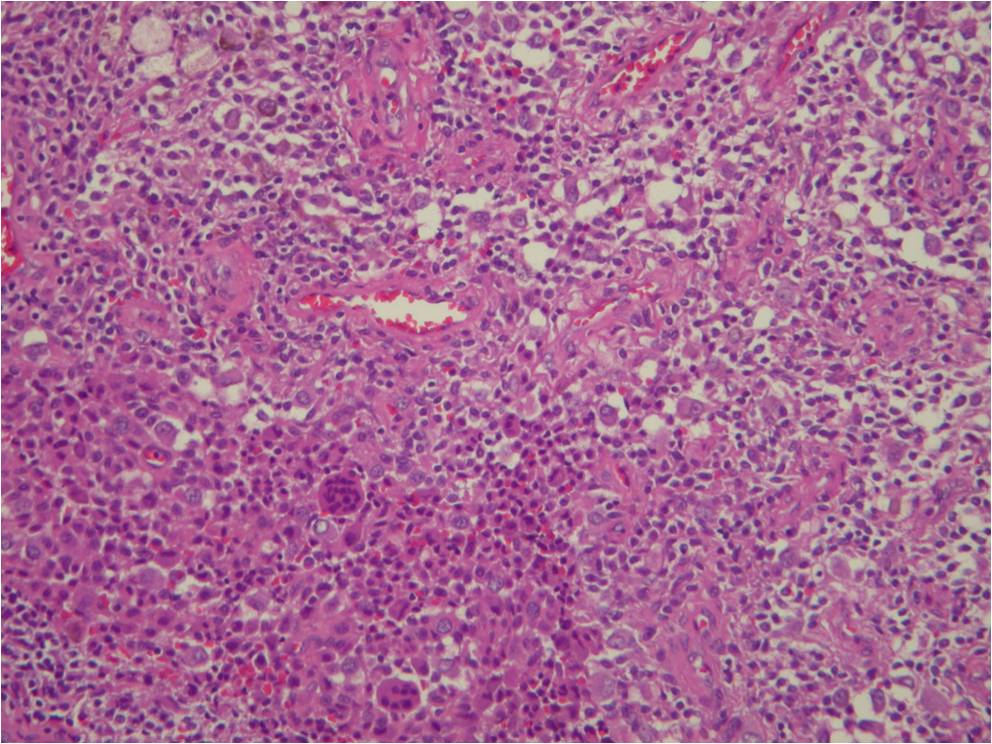

Microscopic

• Dense fibrous tissue divides tumor

• Gives nodular appearance

• Cells

• Small, round to oblong, often reniform or clefted nuclei

• Sometimes prominent nucleoli

• Oblong

• Frequently blend with spindled forms

• Variable numbers of giant cells

• Similar type of nuclei

• Usually contain 8-10 nuclei

• Xanthoma cells

• Sparse mitotic figures

• Low mitotic activity (3 to 5 mitosis x 10 HPF)

• Rarely necrosis is seen

Fig. 7-10: Microscopic pathology. Abundant small hystiocyte-like cells, numerous giant cells and xanthoma cells. In higher magnification images some foamy histiocytes are visible. No mitotic activity is present. Hemosidering deposition is common.